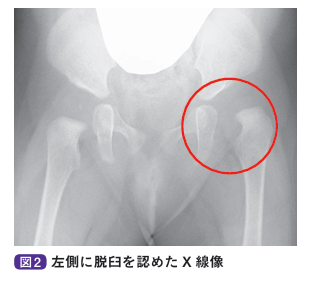

以前までは、奇形や麻痺などの合併がない乳幼児の股関節脱臼を認める状態を「先天性股関節脱臼」とよんできました。しかし、発症原因として母胎内での胎位以外に、出生時には股関節が完全脱臼していなくても寛骨臼形成不全(股関節の屋根となる寛骨臼の形成が悪い状態)のある症例や、出生後の抱き方、オムツの種類、おくるみの巻き方などにより脱臼してくるような後天性の症例があることから、最近では発育性股関節形成不全という呼称が一般的に用いられています。女児、家族歴、第1子、骨盤位分娩、冬生まれは発育性股関節形成不全のリスクが高くなるため、出生時より注意が必要です。

基本的に自覚症状はなく、股関節を90°以上に曲げてから外転した際に開排制限を認めます。股関節を開排したときに股関節が脱臼し、整復する際に指で音を感じた場合はクリックサイン陽性と判断します。一般的には、大腿皮膚溝は左右とも1~2本ですが、脱臼している場合は下肢の短縮により溝の数が増え、溝が深くなります。また、仰向けで両股関節・両膝関節を曲げて、両膝をそろえた際に膝の高さが異なることをアリスサイン陽性といいます。股関節脱臼があると大腿骨の長さが短くなるため、脱臼側の膝が低くなります。

基本的には単純X線像や超音波の検査を行います。そのほかに、必要に応じてMRIや股関節造影などを行う場合もあります。